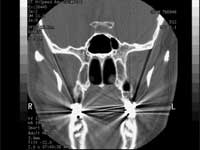

Some experts have suggested that apparent increases in the number of brain cancers might reflect the use of sophisticated imaging techniques like computed tomography and magnetic resonance imaging."However, the fact that the incidence of gliomas, especially the more malignant varieties, is increasing warrants action on this issue," wrote Pawl.

A Swedish research earlier this year, indicated an increased risk of brain cancers (gliomas) as well as acoustic nerve tumors (neuromas) in people using cell phones for ten years or longer. It said that tumours were more likely to develop on the same side as the cell phone was used.